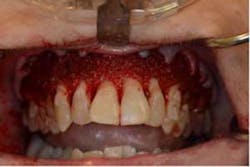

SFOT surgery was performed in the maxillary and mandibular arches with deep buccal corticotomies. Particulate, demineralized, freeze-dried bone allograft and acellular dermal matrix were used to augment the ridges.

Total treatment time: 6 months. Patient declined recommended further clear aligner refinement and fine-tuning periodontal plastic surgery.